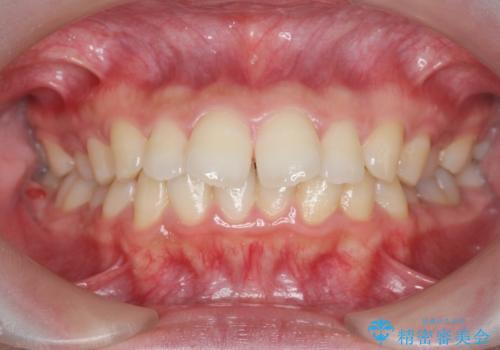

出っ歯を治すマウスピース矯正

- 出っ歯のように見える前歯の角度を治したい、と矯正治療を希望され来院されました。

抜歯をせずにマウスピース矯正システムインビザラインを用いてしっかりと前歯の角度を改善していきます。

前歯の角度だけでなく内側に倒れ込んでいた奥歯もしっかり起こすことで咬合関係も理想的に仕上げています。